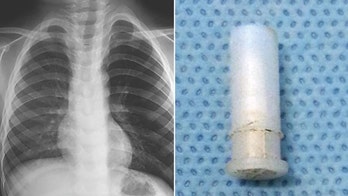

Boy's squeaky cough caused by whistle stuck in his throat He had accidentally inhaled a toy whistle while playing with it.